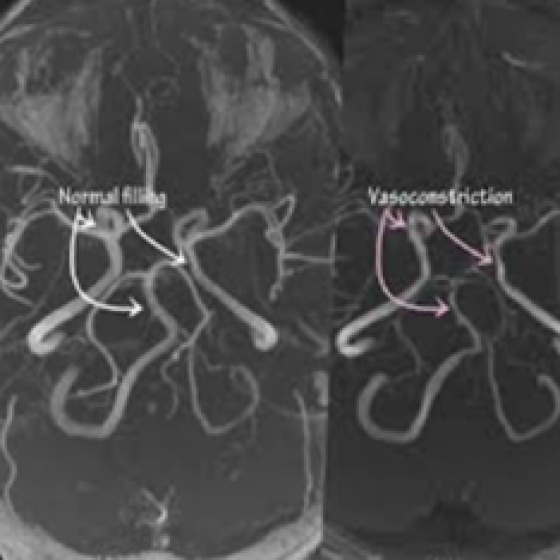

As varreduras de imagem (Screaning) costumam ser a ferramenta mais útil para o diagnóstico de síndrome de vasoconstrição cerebral reversível (SVCR). Os profissionais de saúde podem usá-los para “ver” o cérebro e encontrar problemas. Alguns exames de imagem podem observar o fluxo sanguíneo e o estreitamento dos vasos sanguíneos, enquanto outros podem mostrar áreas que não estão recebendo fluxo sanguíneo suficiente.

As varreduras de imagem que podem ajudar no diagnóstico de SVCR incluem:

- Varreduras de tomografia computadorizada (TC), especialmente angiotomografias.

- Exames de ressonância magnética (RM), especialmente Angio RM.

- Ultrassonografia Doppler transcraniana.

Pessoas com síndrome de vasoconstrição cerebral reversível (SVCR) podem precisar fazer uma tomografia computadorizada e uma ressonância magnética. Uma tomografia computadorizada com contraste é mais rápida e pode ajudar a diagnosticar ou descartar um acidente vascular cerebral, pois pode detectar bloqueios de vasos sanguíneos dentro do cérebro.

Uma ressonância magnética ou ressonância magnética é muitas vezes necessária quando um profissional de saúde descarta um acidente vascular cerebral. Isso ocorre porque uma ressonância magnética ou Angio RM, pode mostrar vasoespasmo no momento em que ocorre ou mostrar quaisquer efeitos persistentes após sua interrupção. Se a tomografia computadorizada e a ressonância magnética não forem suficientes, seu médico poderá solicitar imagens diagnósticas mais precisas como a angiografia cerebral digital por subtração GERAR UM LINK PARA ESSE EXAME